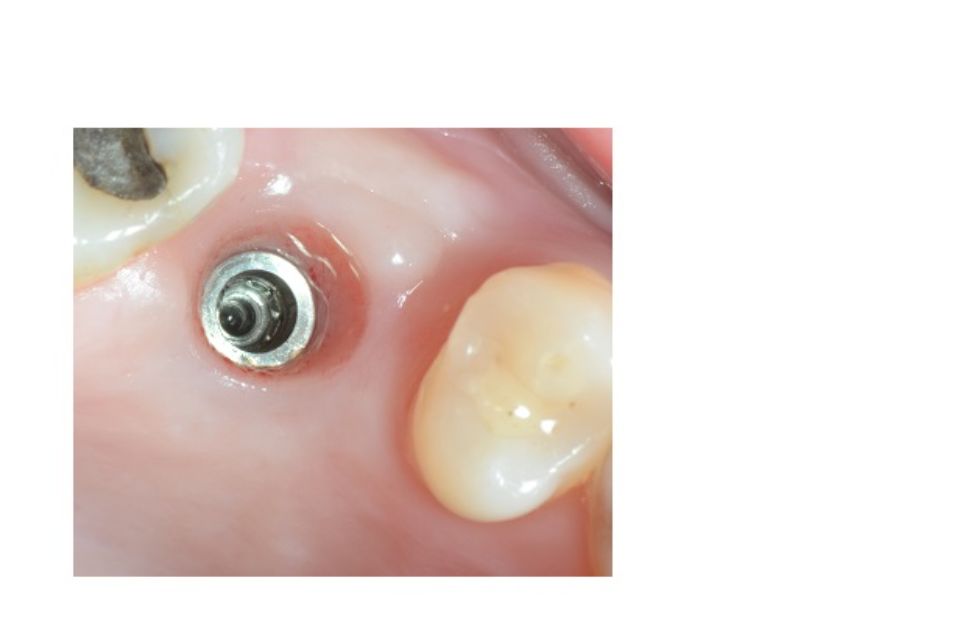

Implantología bucal

La implantología es la especialidad odontológica que se ocupa de la sustitución de la raíz del diente perdido.

La sustitución se hace mediante una pequeña intervención quirúrgica para colocar una pieza de titanio dentro del hueso maxilar.

El implante tiene una rosca en su interior donde posteriormente se enroscará el pilar que soportará la corona protética.

La demora en la reposición de dientes comporta alteraciones funcionales y anatómicas del aparato buco dental, tales como: la reabsorción del hueso maxilar, migraciones y desplazamientos de dientes remanentes o alteraciones fonéticas, estéticas, masticatorias, etc...

Después de la valoración del implantólogo y un diagnóstico muy esmerado por parte del equipo profesional se plantean diferentes soluciones. Dependiendo del problema planteado que puede ser: pérdida unitaria, pérdida múltiple o desdentado completo...se realizará la técnica precisa con el fin de mejorar la calidad de vida del paciente.

La implantología es una de las áreas médicas que más ha evolucionado en los últimos años. Eso hace que la fiabilidad y la comodidad del paciente aumente.